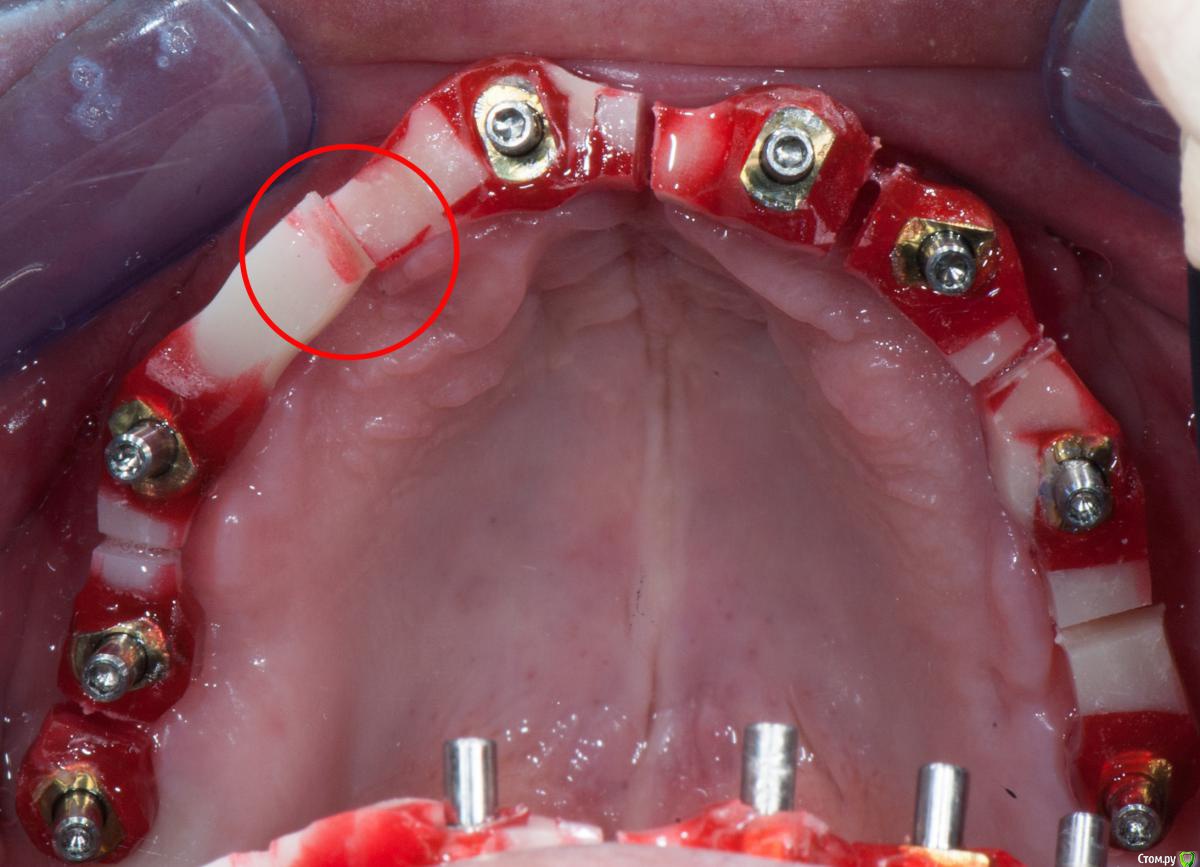

Doc Опубликовано 25 июня, 2017 Поделиться Опубликовано 25 июня, 2017 Не поленился, нашел папочку, в которую старательно складывал такие случаи много лет назад. Сейчас давно уже не было, но тогда, лет десять назад, я каждый случай документировал, чтобы легче было объяснять людям зачем нужен трансферчек. А вот тут уж совсем вопиющий случай, когда техник чебурашку не той стороной засунул в закрытую ложку. С тех пор я только сам лично рассовывал трансферы по слепкам. Ссылка на комментарий

Doc Опубликовано 25 июня, 2017 Поделиться Опубликовано 25 июня, 2017 Doc,классное видео,а есть еще? Скажите,восковой валик на жестком базисе он к имлантам за счет чего фиксируется?Это временные абатменты,соединенные с жестким базисом?Да, временные абатменты на жестком светоотверждаемом базисе. Достаточно прикрутить по трем точкам, чтобы получить нормальную жесткую фиксацию. Все шесть винтов крутить нет смысла. В этом случае два винта спереди, два сзади, но это уже с запасом. Ссылка на комментарий